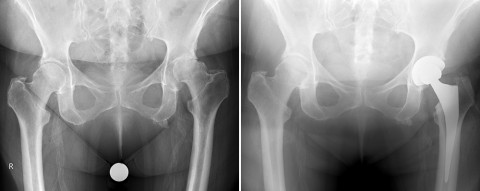

Fall 3: 60-jährige Patientin mit einer schweren rheumatoiden Arthritis (RA)

Infolge der Erkrankung kam es zu einer Durchblutungsstörung des Oberschenkelknochens. Dadurch brach dieser im Kopf-Bereich (Hüftkopfnekrose) ein, was zu stärksten Schmerzen sowie einer Verkürzung des betroffenen linken Beines von gut einem Zentimeter führte. Die Patientin war in ihrer Beweglichkeit und Mobilität nahezu komplett eingeschränkt. Nach operativer Versorgung in minimalinvasiver Technik konnte die Patientin mit vollem Körpergewicht belasten, die quälenden Schmerzen waren bereits kurz nach der Operation stark gebessert. Die Beinlänge konnte komplett ausgeglichen werden.